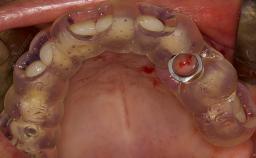

- intraoperative complications of lateral window sinus floor elevation

- intraoperative complications of transcrestal sinus floor elevation

- postoperative complications of sinus floor elevation